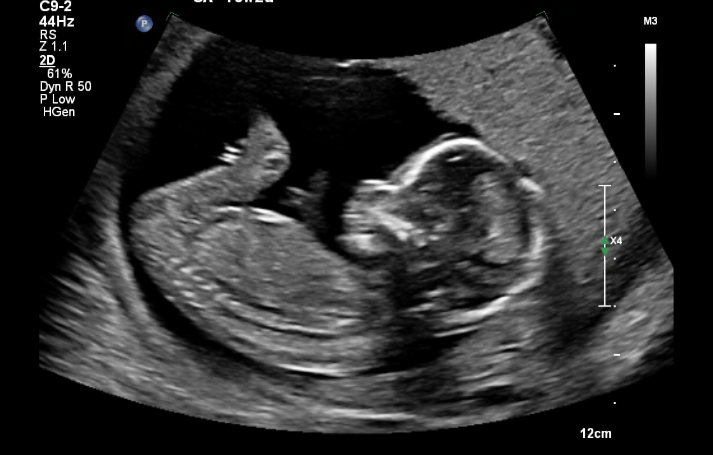

- 10~12주차 초음파(Ultrasound) 스캔 및 피 검사: 임신 초기 아기의 비정상적 발달 및 유전자 검사

- 20주 차 초음파 검사: 임신초기에 다 만들어진 장기 아나토미 검사 (예: 뇌, 심장 발달, 콩팥 등등)

이 때의 두번은 반드시 초음파와 피 검사를 해야한다. 그 외에 초음파는 미드와이프의 요청에 따라 추가적으로 할 수 있는데, 나의 경우는 10주, 12주, 15주 그리고 20주 이렇게 총 4번의 초음파 검사를 시행했다. (임신부가 요청해서 뭐 2주나 1주에 한번씩은 할 수 있는지는 잘 모르겠다)